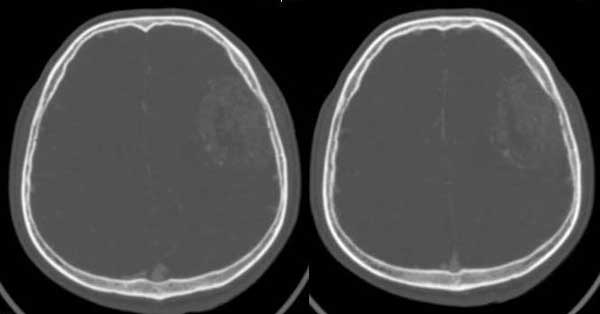

左颞部稍低密度d形肿块影阴,密度不均,内有不规则囊变区,局部脑白质受压塌陷,肿块周围少许水肿带,中线轻度右移位,增强扫描明显强化,局部颅板有轻微侵蚀,如此大的肿块中线结构移位不明显说明肿块位于脑外,如此强化的脑外肿瘤只有一个------脑膜瘤

左颞区脑膜瘤,主要压迫颞叶。

定位:脑灰白质界面内移,肿瘤位于脑外,应该明确。

定性:支持脑膜瘤。

本例我首先考虑脑膜瘤,但其具有形态不规则、密度不均匀、有明显的坏死液化、没有完整和明显的包膜、且呈明显不均匀性强化等诸多恶性特点,应该首先考虑恶性脑膜瘤(但颅骨只有轻微受压而没有明显的受浸润破坏现象也不太支持)。

还有不支持的地方,比如那么大地肿瘤而瘤周水肿不明显。所以,我第2考虑海绵状血管瘤。建议mri检查。

左侧颞顶叶见d形肿块灶,密度不均,其内可见低密度影,局部脑白质所压移位,病灶明显强化。支持脑膜瘤